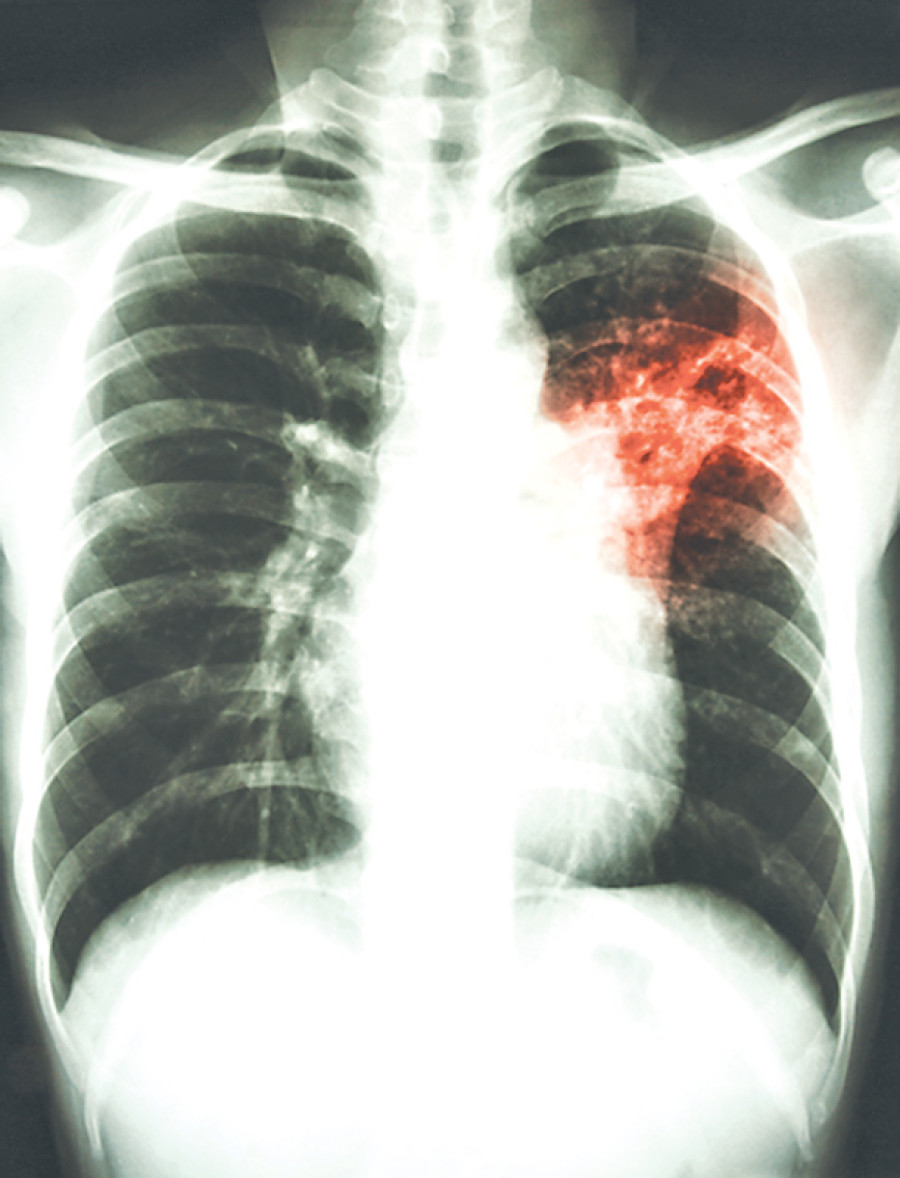

The World Health Organisation (WHO) reported that the ‘ancient’ lung disease tuberculosis (TB) now ranks alongside HIV as a leading cause of death worldwide. Although Nepal is not listed as one of the most at-risk countries because of TB, the devastating earthquakes that hit in April and May 2015 left many individuals displaced and have caused significant problems in getting vital medication to those in need.

As an airborne infectious disease, if someone who is infected with TB is left untreated, they can infect up to 15 others around them in a year. According to the NTC, 45 percent of the population in Nepal has been infected with TB; 80,000 people are currently suffering from TB and over 40,000 new cases are occurring every year. The highest rates of infection have been found in the most densely populated areas. This implies that those displaced individuals who are currently living in the temporary settlement camps are prone to TB simply because they are forced to live in less-than-optimal conditions, often with poor ventilation, overcrowded, stressful conditions, and inadequate nutrition.